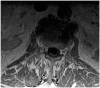

West Nile virus infection poses a significant threat, especially during the warmer months when mosquitoes are abundant. Clinicians must remain vigilant for neuroinvasive illness in patients presenting with febrile symptoms and malaise following mosquito exposure. While magnetic resonance imaging and cerebrospinal fluid analysis aid in differential diagnosis, detecting West Nile immunoglobulin M in serum is crucial for definitive diagnosis. Treatment primarily involves supportive care due to the absence of established regimens, though promising outcomes have been reported with plasma exchange and intravenous immunoglobulin. We present the case of an 83-year-old resident of Alabama, an avid gardener living near a pond, who initially exhibited symptoms of productive cough, diarrhea, fever, and generalized malaise. However, within 48 h, he developed hypoxemia, functional quadriplegia, and bulbar palsy necessitating intubation. Diagnostic evaluations, including magnetic resonance imaging and positive West Nile virus immunoglobulin M in serum, confirmed West Nile virus-associated poliomyelitis viral syndrome, prompting intravenous immunoglobulin therapy. This case highlights the importance of promptly identifying and managing West Nile virus infection, especially in regions susceptible to mosquito-borne diseases, and being vigilant of the disease in non-endemic regions. The case also begs the question of the timing and efficacy of intravenous immunoglobulin and plasma exchange in West Nile virus infection and the fact that more data should be collected on these therapies.

Keywords: West Nile encephalitis; West Nile neuroinvasive disease with poliomyelitis syndrome; West Nile virus; caudal nerve root enhancement; flavivirus.